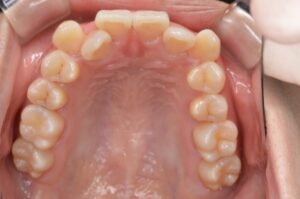

①写真撮影

今の歯並びを色々な角度から撮影します。

せっかくなので矯正前→現在(No.40)で並べてみます。